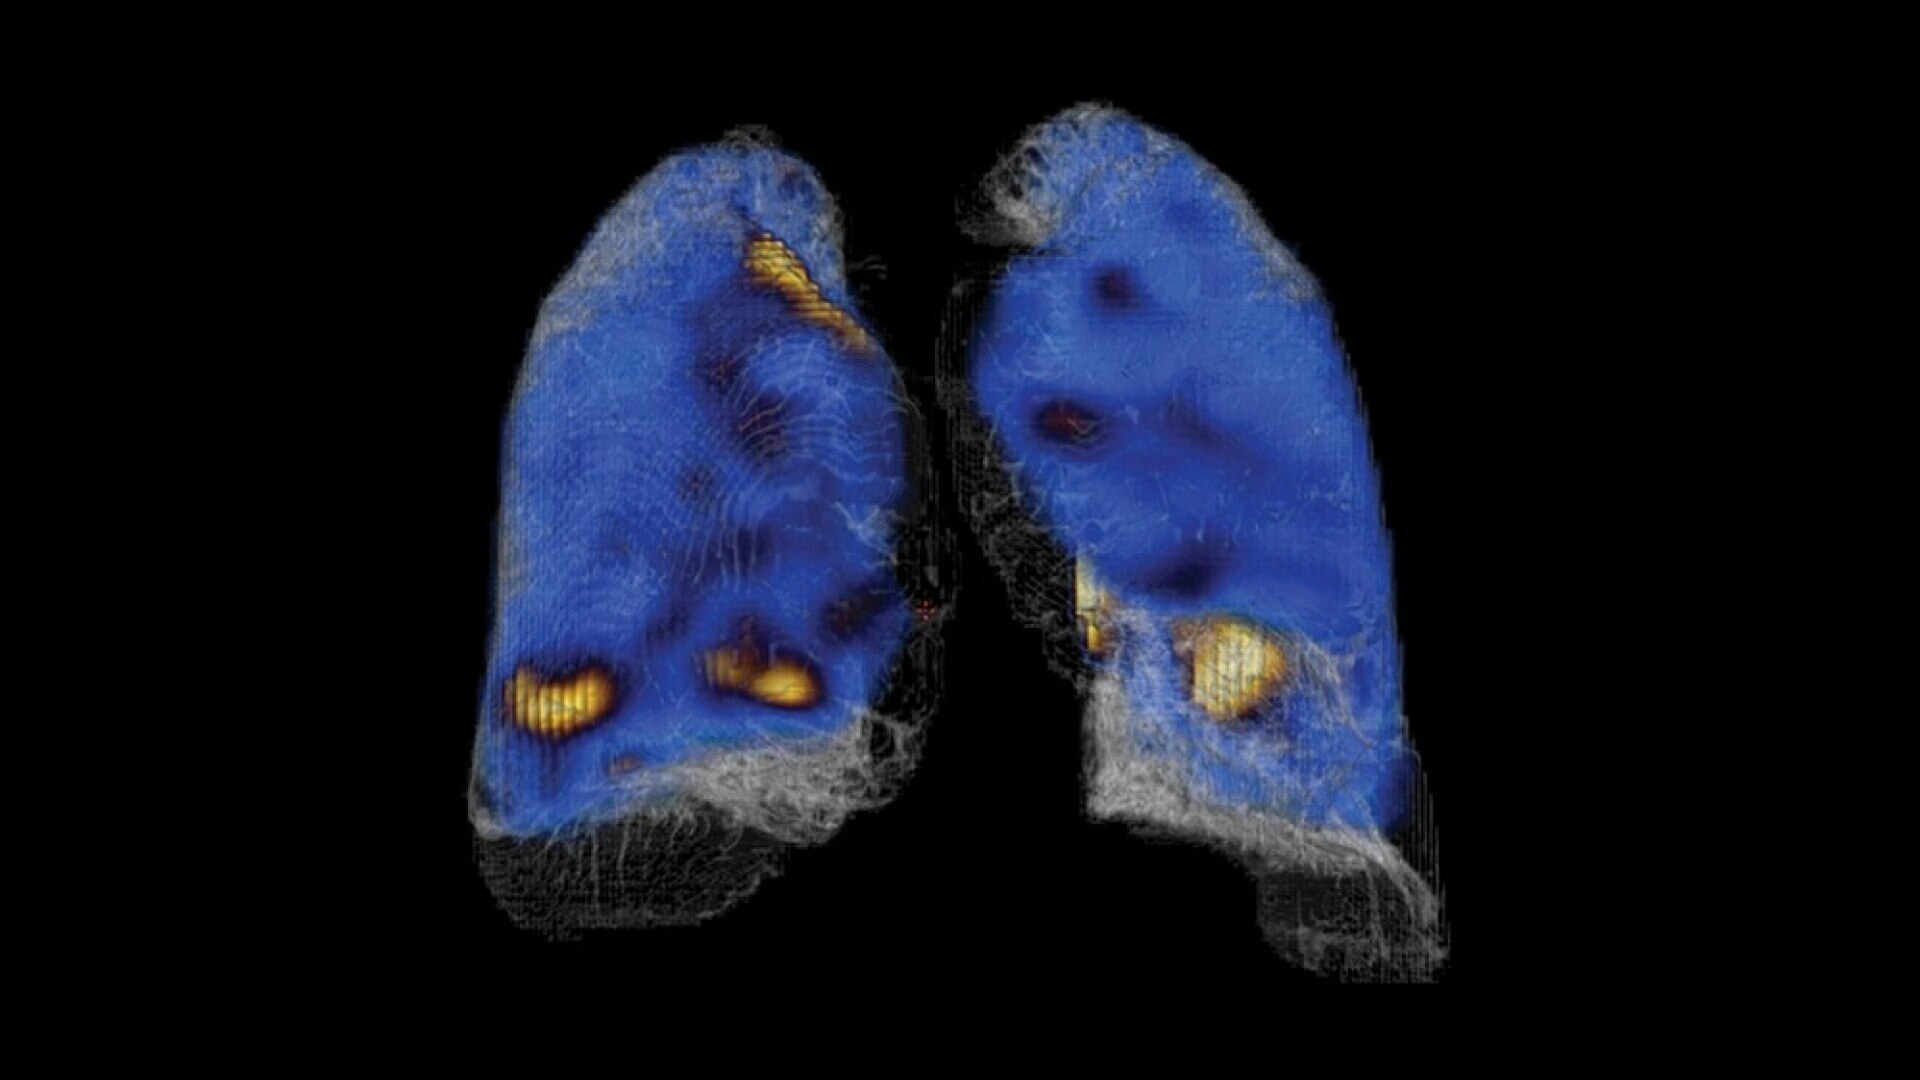

See everything clearly now

As molecular imaging continues to move toward the development of disease-specific diagnoses and increasingly personalized care, resolution is important. Early disease detection is only possible with a high system resolution that enables visualization of finer anatomic detail.

The resolution to discover something new

With direct conversion detection, NM/CT 870 CZT has substantially improved system resolution⁴ by eliminating the signal loss and noise that comes with analog detection technology. It also uses a registered collimation design that aligns each collimator hole with a single detector pixel. This design eliminates the impact of collimator resolution that would normally affect the overall system resolution. The result is an improved contrast-to-noise ratio⁵ and spatial resolution down to 2.8 mm.⁶